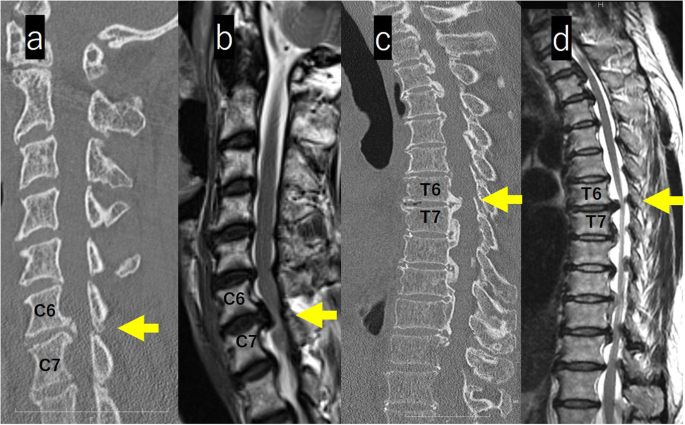

On computed tomography (CT) images of the whole spine, isolated OPLL was observed from the lower cervical vertebra to the middle thoracic vertebra. At T6/7, a beak-shaped protrusion into the spinal canal was observed (Figs. 3a, c).

a-d: MRI and CT images of the cervical and thoracic spine. CT images of the whole spine, isolated OPLL was observed from the lower cervical vertebra to the middle thoracic vertebra. At T6/7, a Beak-shaped protrusion into the spinal canal was observed (a, c). MRI revealed stenosis with a spinal cade intensity change at C6/7 and extensive spinal cord compression with a spinal cade intensity change in the thoracic spine (b, d)

Magnetic resonance imaging (MRI) of the whole spine revealed stenosis with an intensity change in spinal cord at C6/7 and extensive spinal cord compression in the thoracic spine (Figs. 3b, d). Contrast-enhanced MRI of the brain showed a mass without contrast enhancement on the right side of the anterior pituitary gland (size, 10 mm × 12 mm × 10 mm) with suprasellar and parasailer extension; the image revealed a pituitary macroadenoma (Fig. 4).